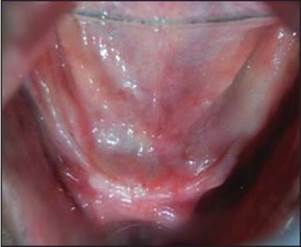

Después de la curación, se eliminaron las extensiones por mucosa y se colocaron análogos de impresión. La impresión de bandeja abierta se realizó con material de impresión elastomérico y se aflojaron los análogos de impresión. El análogo de implante se roscó al análogo de impresión en la bandeja de impresión y se vertió el molde. Se colocó el pilar sobre el yeso y se realizó el montaje. Se llevó a cabo una prueba con metal, luego se realizó la acumulación de cerámica y se fabricó la prótesis final y se verificó en la cavidad oral y se realizó la cementación final [Figura 9] . Las instrucciones de higiene oral postoperatorias se dieron al paciente y se realizó un seguimiento adecuado (Kim, Misch y Wang, 2005).

Figura 9. Prótesis final